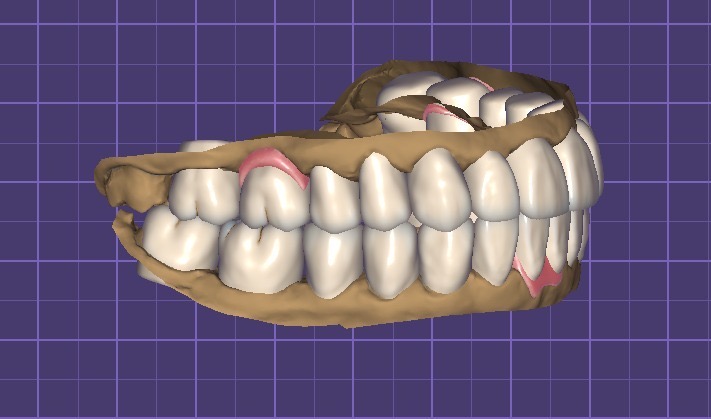

– כתרים ותותבות על גבי שתלים בסריקה ע״י הדפסה ממוחשבת

סריקה ותכנון ממחושב

מעבדה לשיקום הפה, שיקום ושיחזור בעידן השתלים הדנטליים

טיפול ע״י רופא סריקה והרכבה לאחר עיצוב מחשב

שיקום פרוטתי ע״י כתרים מעוכים למתכת: זירקוניה, זירקוניה מונוליתית, תותבות על גבי שתלים ממוחשבים

השחזה סריקה תכנון ועיצוב וביצוע ע״י הדפסה או חריטה

סריקה מלאה של הפה תכנון ושיקום הדמיית מחשב